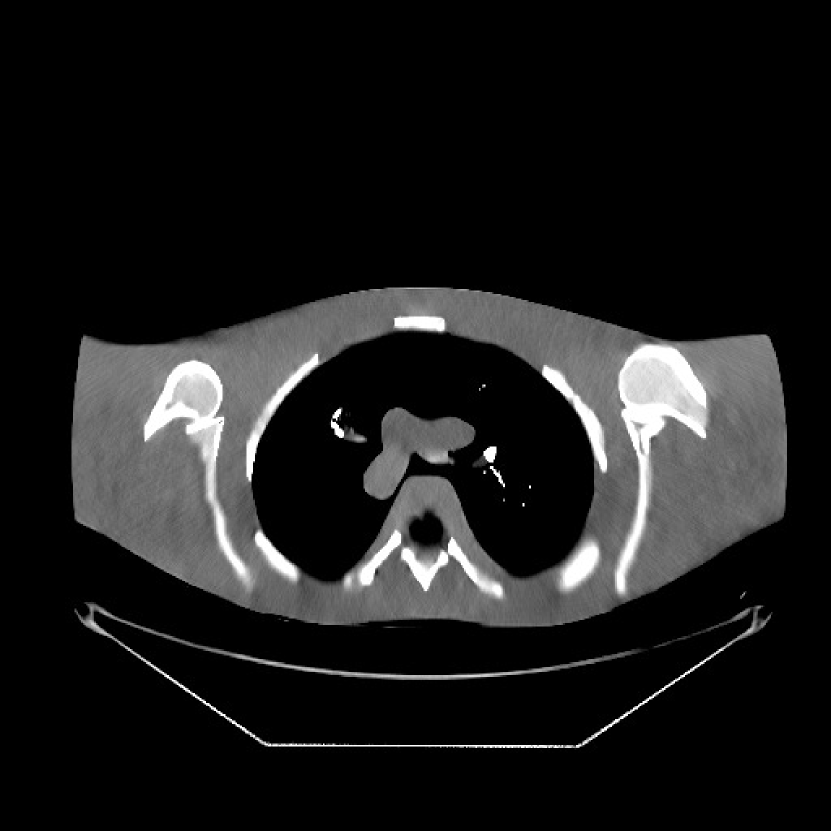

Fig. 9 shows three axial slices from the 3D reconstructions with SPULTRA and PWLS-ULTRA at : the middle slice (No. 67) and two slices located farther away from the center (No. 90 and No. 120). The image profiles along a horizontal line (shown in green) in the displayed slices are also shown in Fig. 9. The reconstructed slices using PWLS-ULTRA appear darker around the center compared to the “true” clinical image and the reconstructions with SPULTRA. This means PWLS-ULTRA produces a strong bias in the reconstruction. The bias can be observed more clearly in the profile plots: the pixel intensities for the SPULTRA reconstruction better follow those of the “true” clinical image, while those for the PWLS-ULTRA reconstruction are much worse than the “true” values. Moreover, SPULTRA achieves sharper rising and failing edges compared to PWLS-ULTRA. In other words, SPULTRA also achieves better resolution than PWLS-ULTRA. Fig. 9 also shows a zoomed-in ROI for each of the chosen slices, and highlights some small details with arrows. It is clear that in addition to reducing the bias, SPULTRA reconstructs image details better than PWLS-ULTRA.